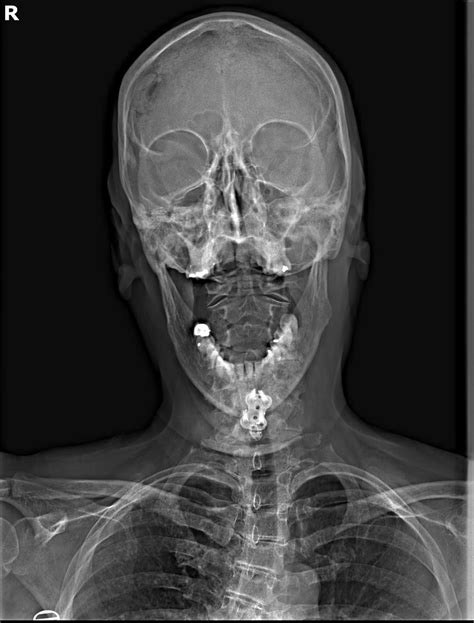

Measuring the Angle of Cobb

Measuring the Angle of Cobb involves several steps, typically performed using X-ray images. Here is a detailed guide on how to measure the Angle of Cobb:

1. Obtain a standing posteroanterior (PA) X-ray of the spine.

2. Identify the most tilted vertebrae above and below the apex of the curve.

3. Draw a line along the endplate of the most tilted vertebra above the apex.

4. Draw a line along the endplate of the most tilted vertebra below the apex.

5. Draw perpendicular lines to these endplate lines.

6. Measure the angle formed by the intersection of the perpendicular lines.

This angle is the Angle of Cobb and represents the degree of spinal curvature.

📝 Note: It is essential to ensure that the X-ray images are of high quality and taken with the patient standing upright to obtain accurate measurements.